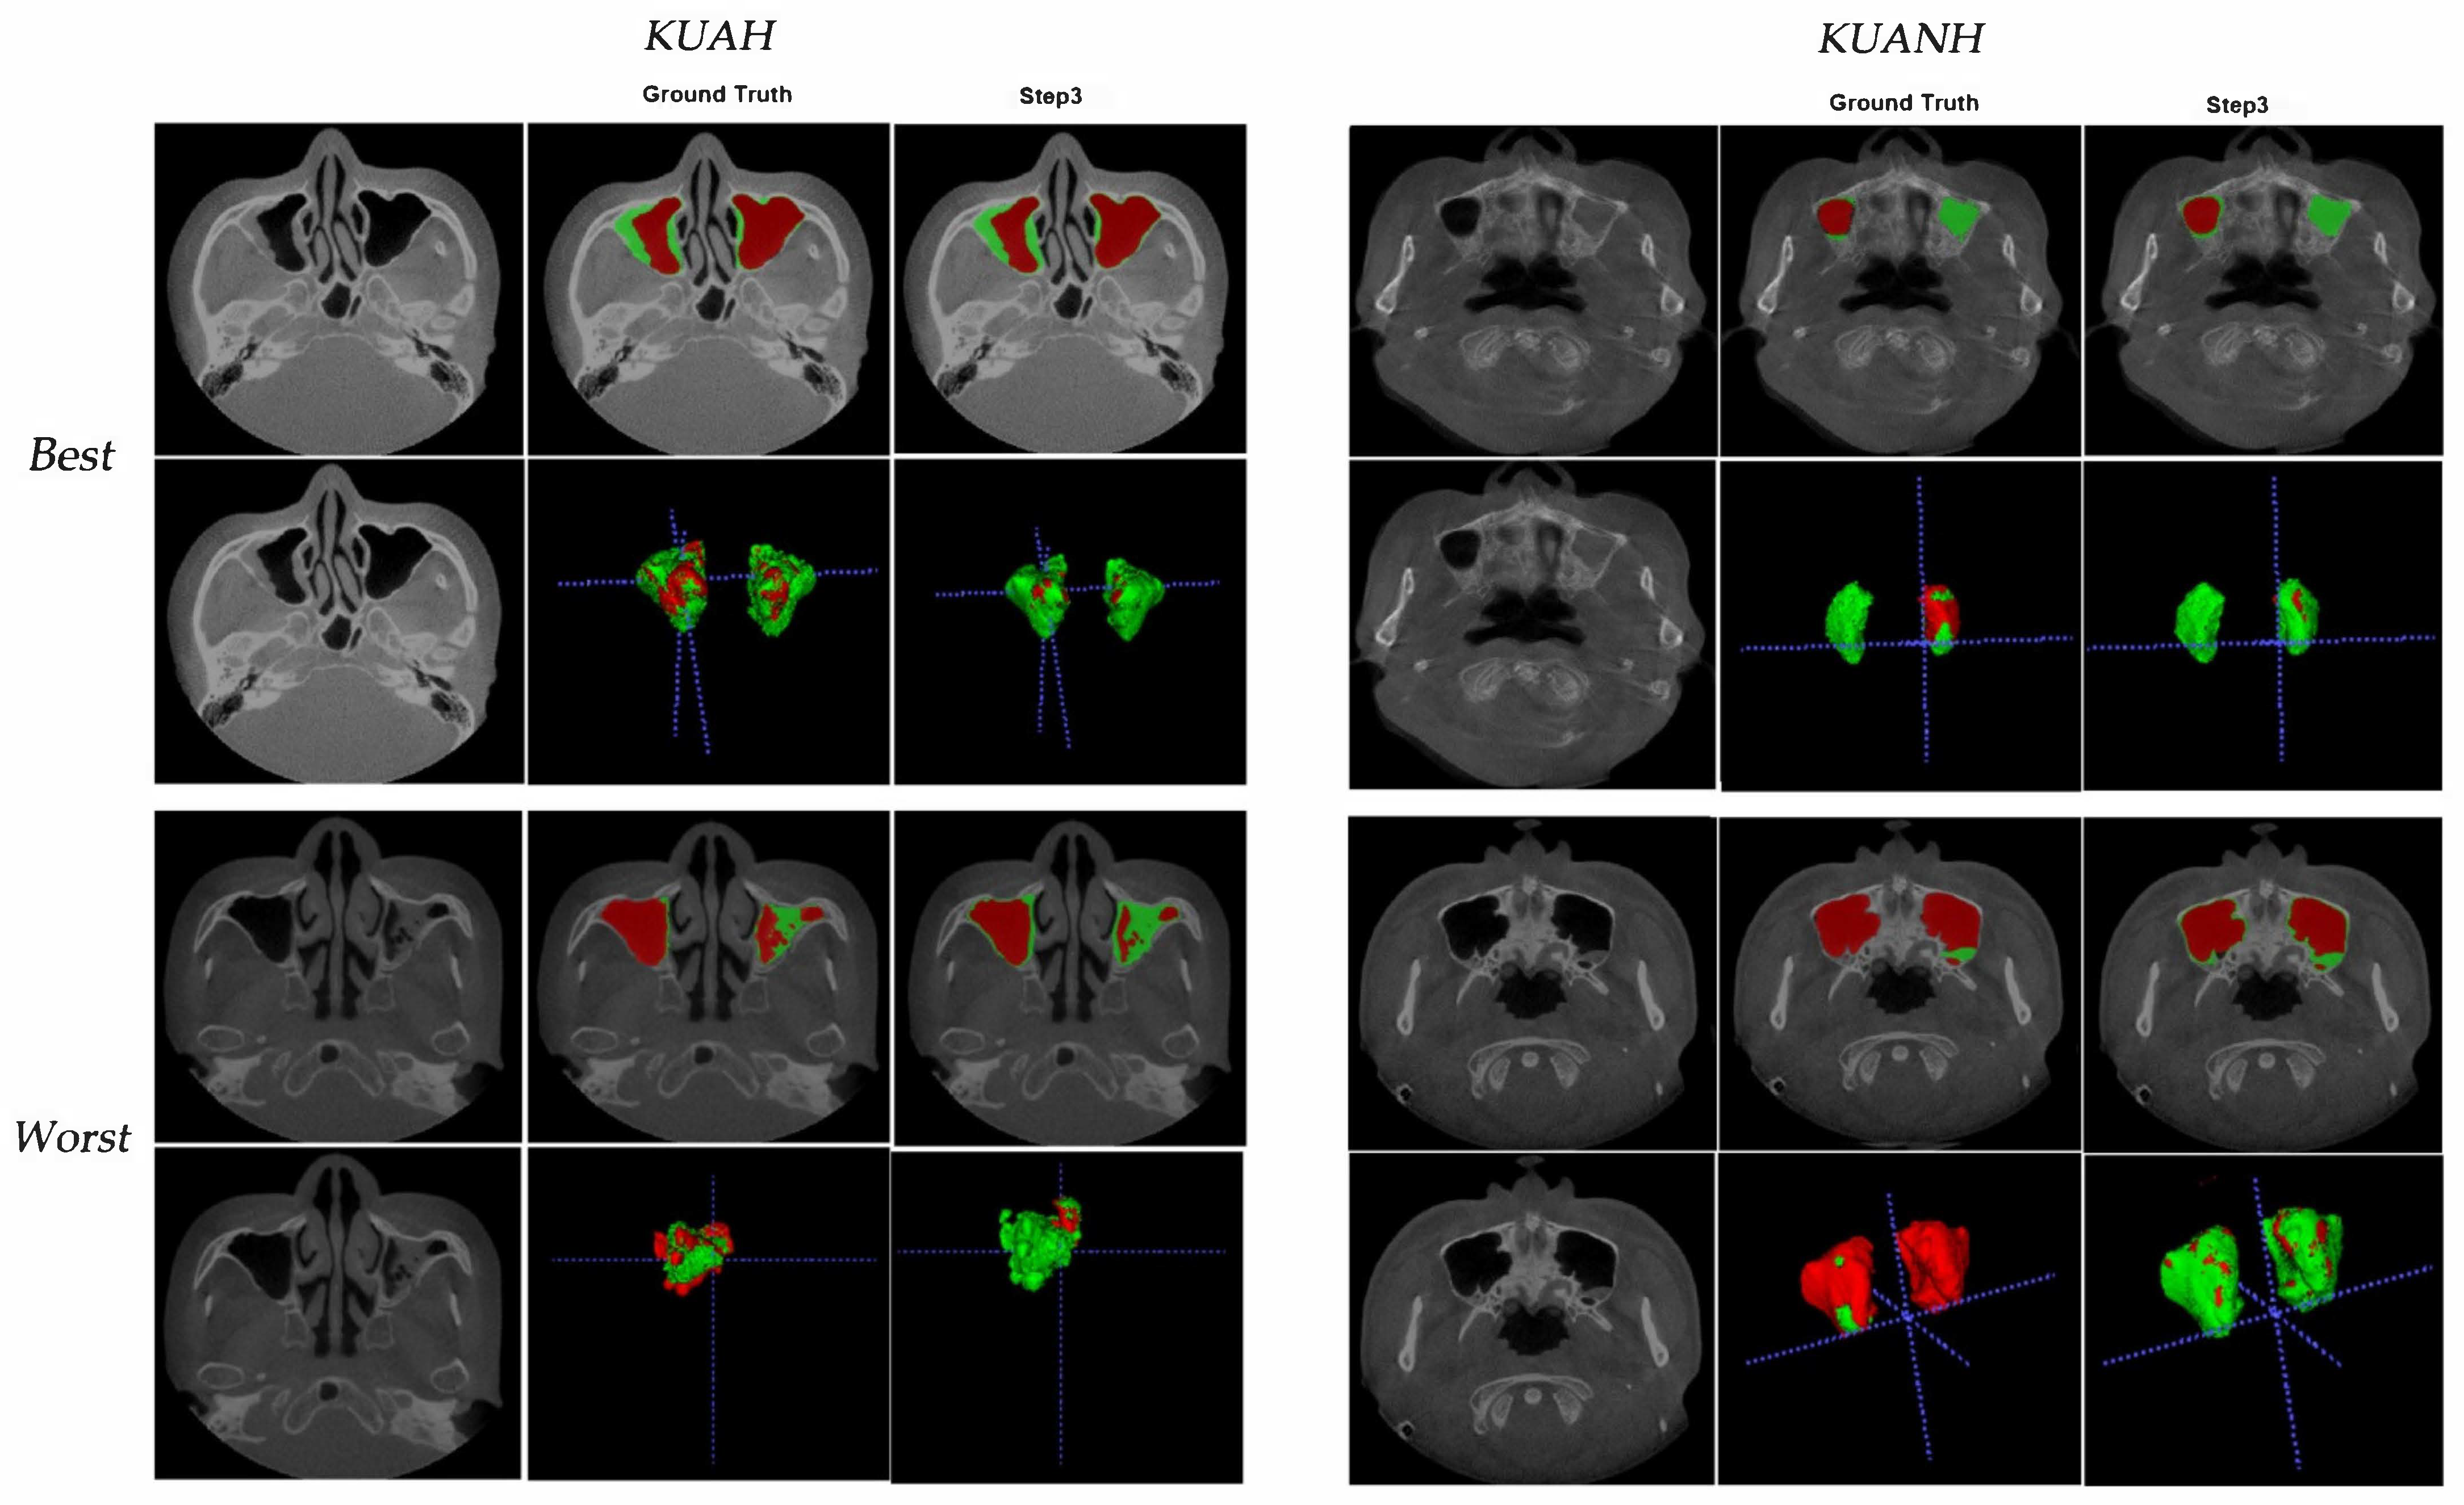

| Mean ± SD (Range) | Last step (KUAH) | Last step (KUANH) |

|---|---|---|

| Air | 0.93 ± 0.16 (0.243–0.996) | 0.97 ± 0.02 (0.94–0.99) |

| Lesion | 0.76 ± 0.18 (0.208–0.96) | 0.54 ± 0.23 (0.12–0.88) |